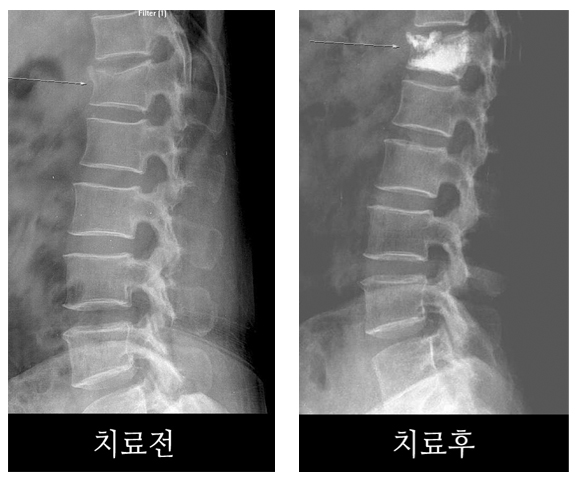

골다공증은 특히 중노년기의 여성에게 흔한 질환으로 뼈의 강도가 약해져 사소한 충격에도 쉽게 부러지는 질환을 뜻한다. 여성의 경우에는 특히 폐경으로 여성 호르몬이 줄어들면서 골다공증이 급속히 진행되는 경향이 있다.

추운 겨울에는 잘 사용하지 않다가 날씨가 따뜻해 지는 봄에는 뼈와 이를 둘러싼 근육이 충분히 풀어지지 않은 상태에서 나들이 중 특히 외부에서 넘어지거나 다치는 경우가 많기 때문에 골다공증을 가지고 있는 이들은 특히 척추골절 등의 주의를 요한다.

골다공증은 일반인과 달리 작은 충격에도 크게 다치는 경우가 많고 치료되는데 시간이 오래 걸리는 편이기 때문에 무엇보다도 예방이 중요하다. 다리나 팔의 골절과 달리 척추 골절의 경우 생활의 불편함이 따를 수 있기 때문에 예방이 중요하다. 척추 골절 예방은 자세를 교정하고 균형감각을 증진시킬 수 있는 훈련을 지속적으로 하는 것이 도움이 된다. 집안에서도 실내조명을 밝게 하고 온도를 춥지 않게 유지하며 실내 바닥은 물론 목욕탕과 같이 미끄러지기 쉬운 곳에서는 손잡이와 발판을 마련하는 것이 좋다.

안산 21세기 병원에서는 정영조 원장을 비롯해 여러 척추 전문의들이 척추 골절을 치료하고 있다. 신개념 네비게이션 치료로 치료 효과는 더욱 높이고 재발률은 낮추는 획기적인 치료법과 다수의 MRI 장비를 통해 대기시간도 줄여 젊은 층은 물론 노년층의 만족도도 매우 높다.